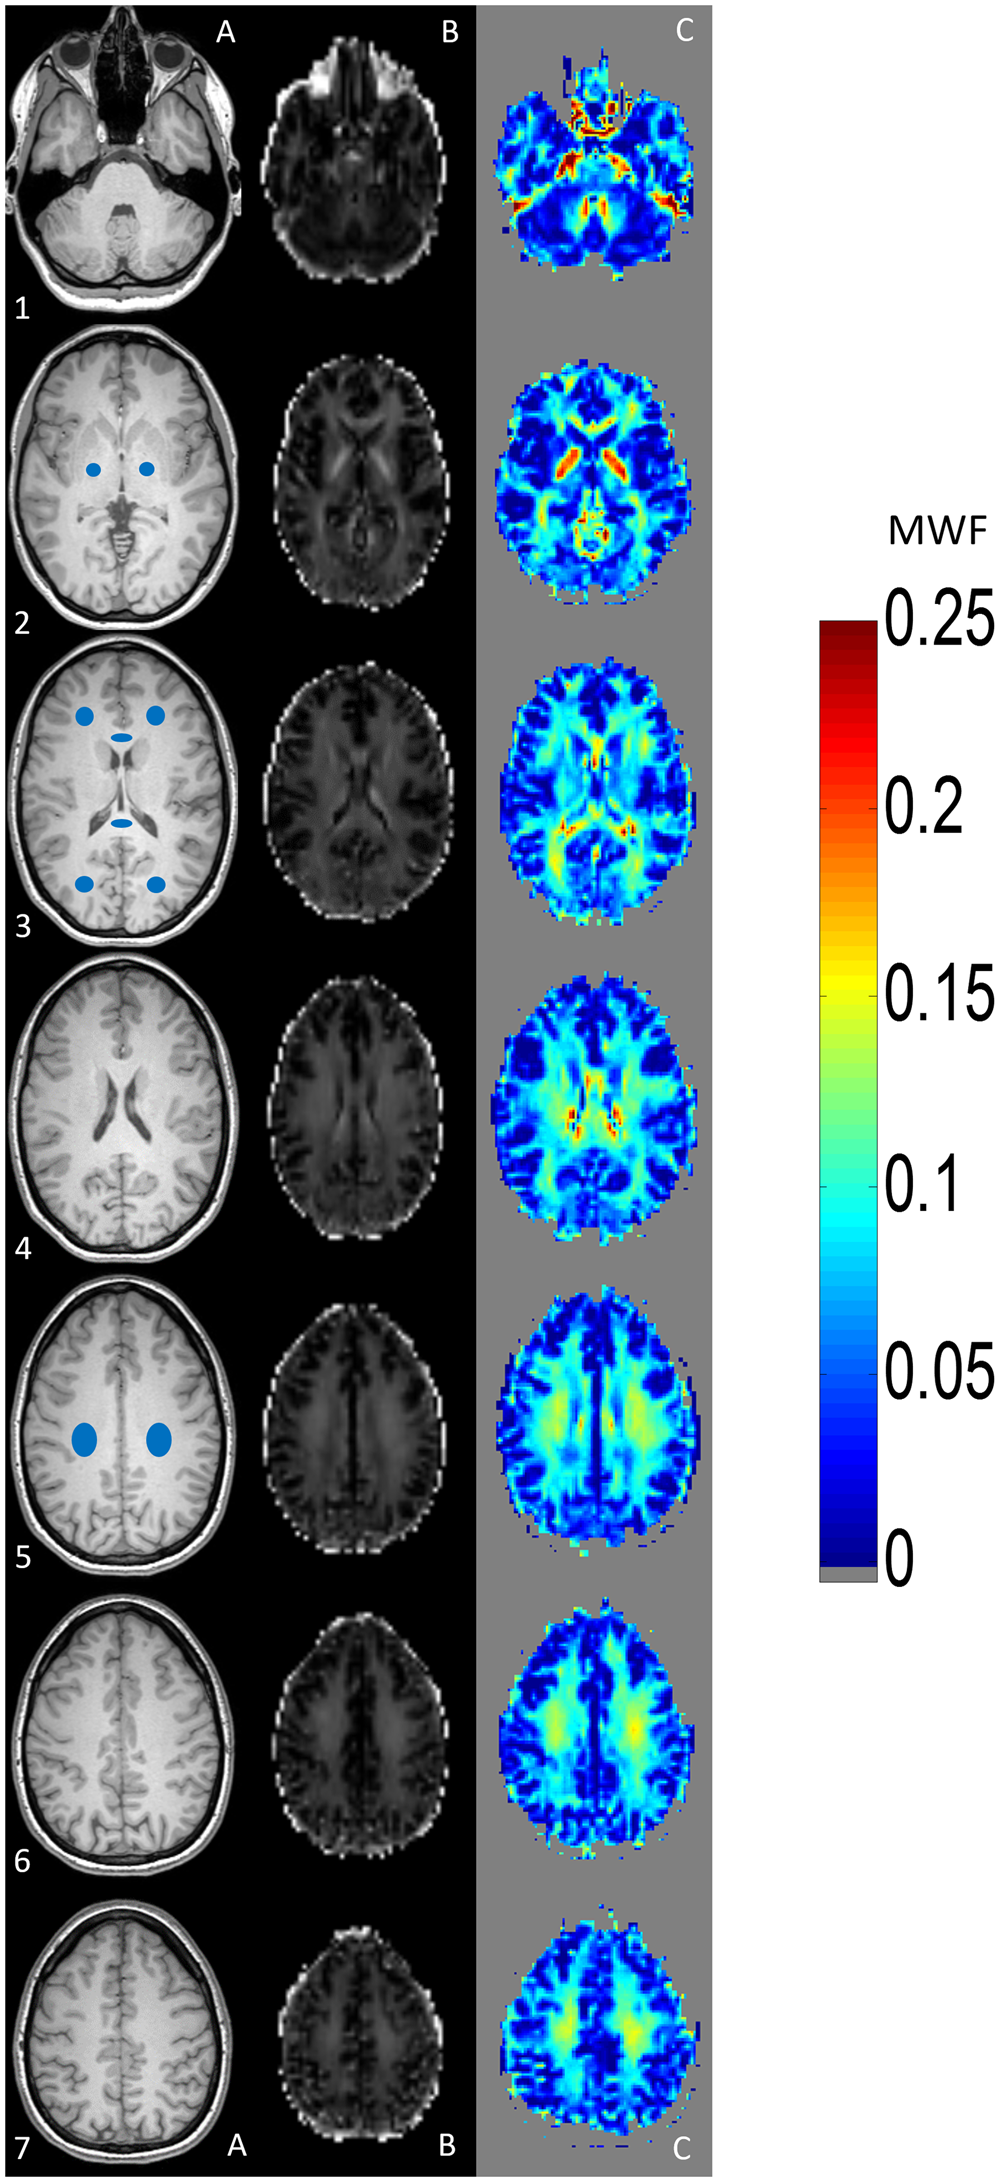

Figure 1

Visualizes a side-by-side comparison between T1-weighted images (left side, column A), the calculated MWF maps (middle, column B) and MWI heat maps (right side, column C). An example for ROI localization is given in column A. The scale on the right side indicates the estimated MWF values. Higher MWF values are indicated by the range of “warm” (red) colours, whereas lower MWF values are indicated by the range of “cold” (blue) colours. ROIs were placed in both corticospinal tracts (section A2), frontal and occipital white matter (WM) and genu- and splenium of corpus callosum (section A3) and the parietal WM of both hemispheres (section A5).